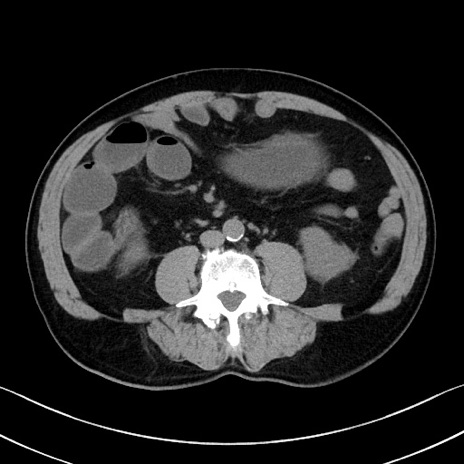

症例35(横断像)

【症例】70歳代 男性

【主訴】腹部膨満、嘔吐

【現病歴】昨日より腹部膨満感出現。本日増悪し、仙痛出現。嘔吐あり、受診。

【既往歴】糖尿病、胆摘後

【身体所見】BP 149/80mmHg、HR 74/min、BT 35.9℃、腹部:膨満、軟、圧痛なし。腸雑音減弱あり。上腹部正中切開瘢痕あり。

【データ】WBC 13500、CRP 1.72